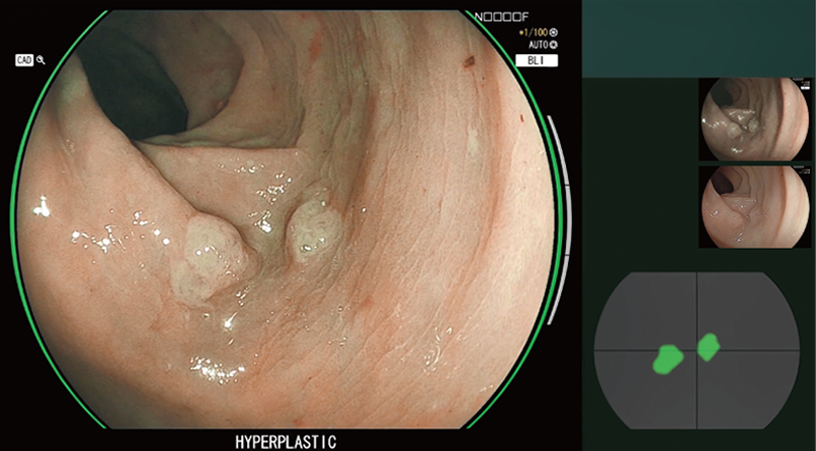

CAD EYE is FUJIFILM's brand name of computer-aided diagnosis (CAD) function for endoscopy. CAD EYE has been developed utilizing AI deep learning technology with an immense amount of clinical images.

Characterization